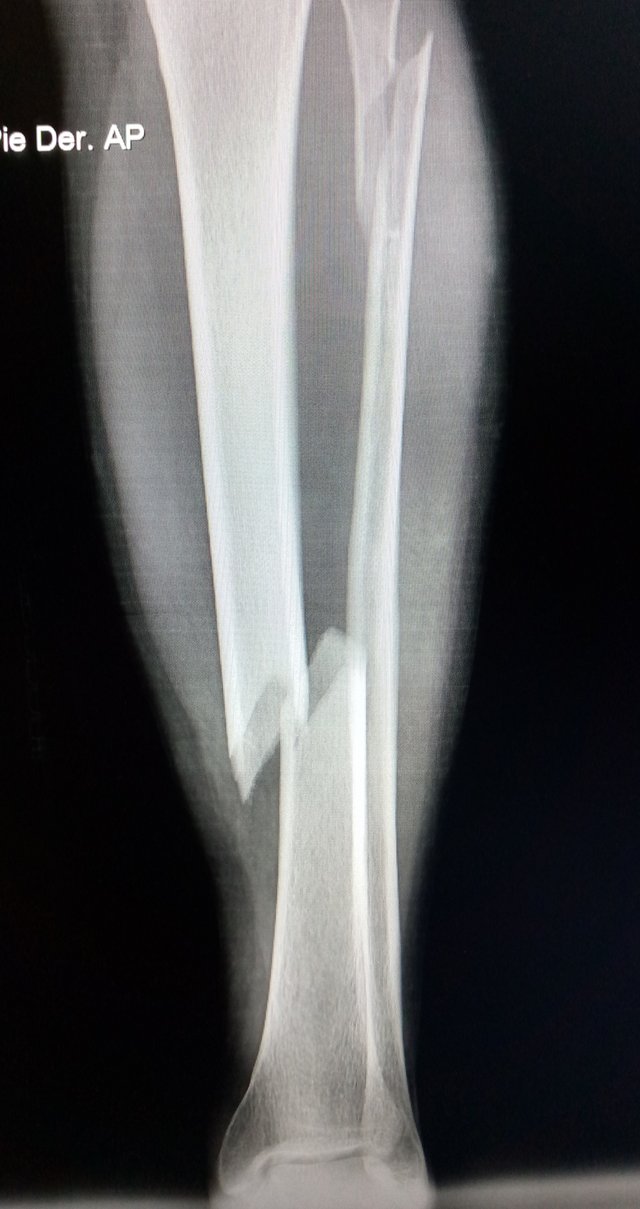

Mi paciente es una joven de 29 años de edad, la cual sufrió un Traumatismo hace aproximadamente 27 días, en miembro inferior derecho, por caída de altura de aproximadamente 2 metros, dejando como consecuencia; fractura distal de tibia y fractura proximal de peroné, ambas con desplazamiento de las piezas óseas, lo cual ameritó tratamiento quirúrgico y cuidados post- operatorios, dejando una inflamación que llega hasta región infra-rotuliana y limitación funcional.